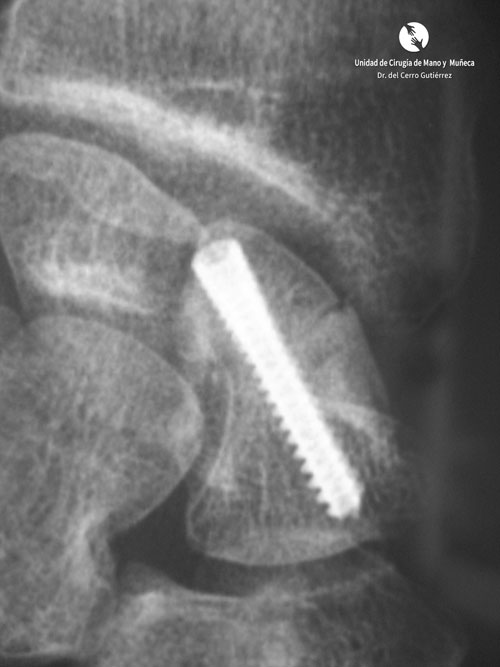

Fractura del Escafoides.Síntesis-Dorsal de Fractura

Síntesis Dorsal de Fractura